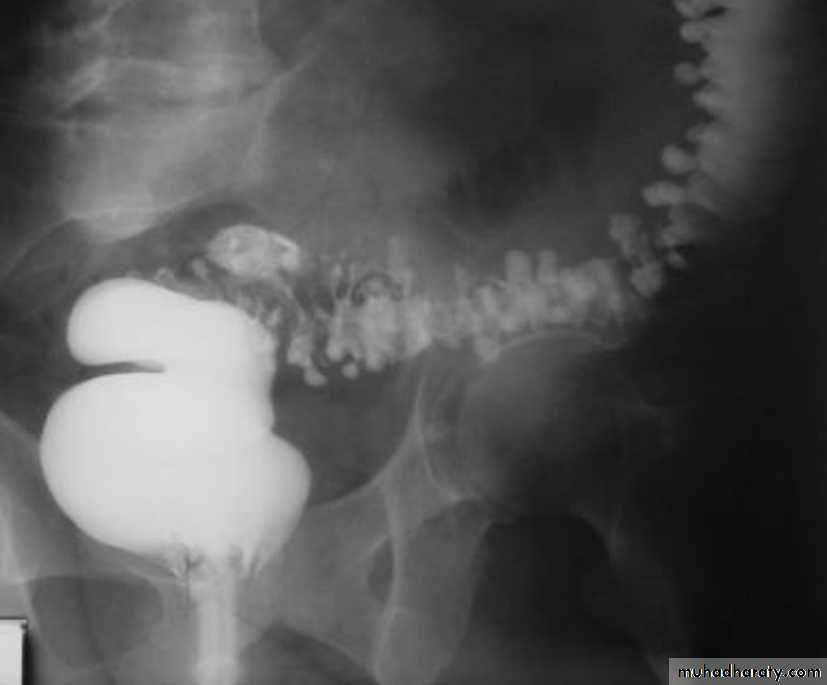

• Morphological types:• 1_ Ulcerative : give rise to irregularity of the colon with ulceration.

• 2_ Constrictive or infiltrative ( Annular ) type :

• a- Constant narrowing .

• b-Shouldering sign, apple core sign .

• c- Destruction of mucosa at narrow area .

• d- Double track due to fistula .

• e- In severe constriction ; stoppage of Ba. Flow with proximal dilatation .

3_Proliferative type : give rise to :

a- Large , constant filling defect with irregular margin .

b- Destruction of mucosa .

c- Intestinal obstruction

apple core lesion in the descending colon